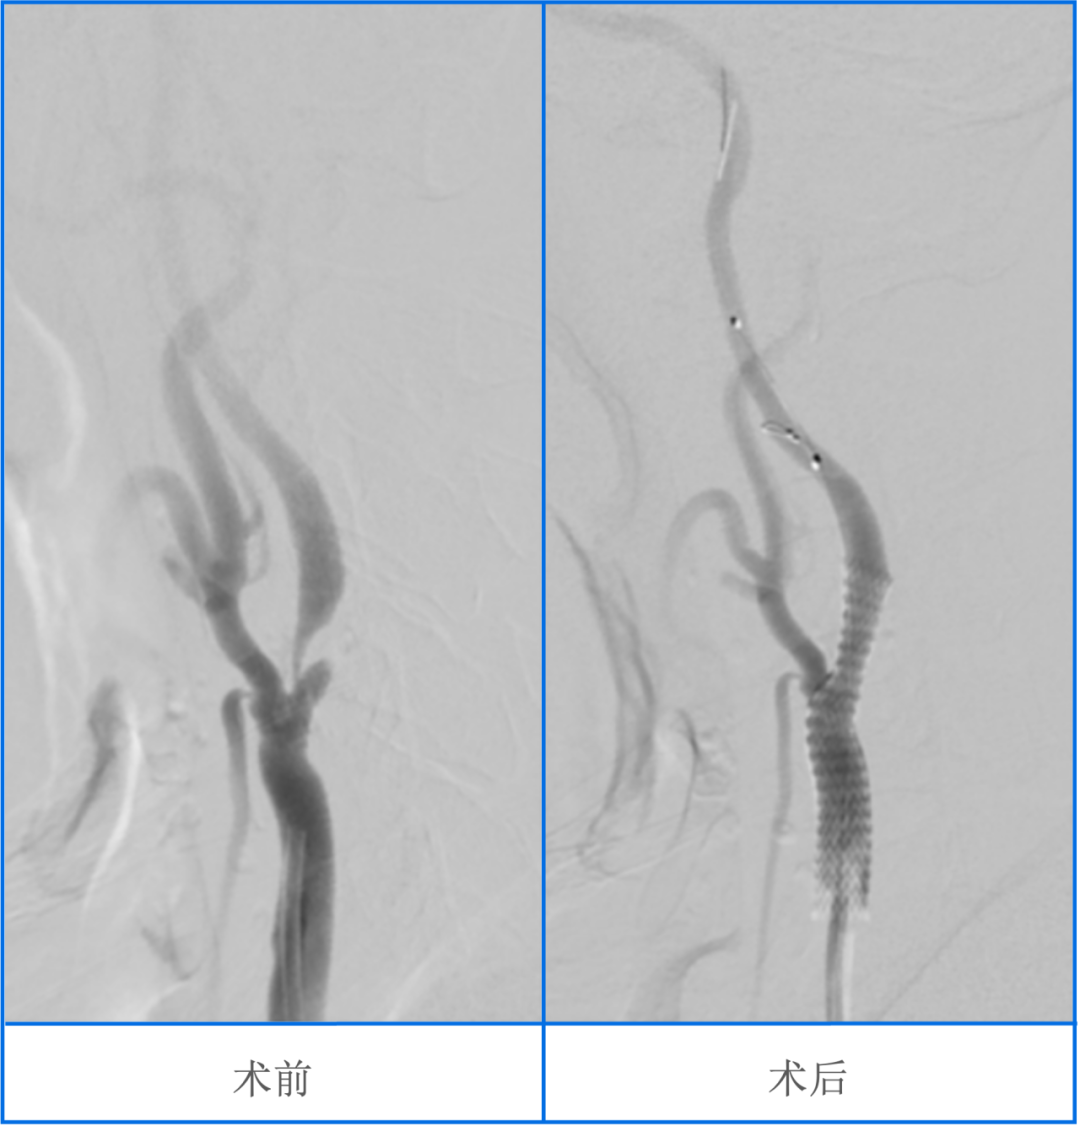

颈动脉狭窄是引起脑梗死的重要危险因素,很多脑梗死患者,是因为颈动脉狭窄导致的脑血流灌注不足,以往认为颈动脉内膜剥脱术能够有效降低颈动脉狭窄引起的脑梗死发生风险,但随着介入技术和器材的发展,颈动脉支架手术逐渐成为一种可以替代颈动脉内膜剥脱术的一种治疗方式,而脑保护伞下颈动脉支架置入术是治疗颈动脉狭窄的一种常规神经介入手术,在评估手术的必要性和安全性后,医生会向患方充分沟通,使其了解手术的基本过程、可能出现的风险及应对办法。以下简述于Spider保护伞保护下对颈动脉狭窄置入PRECISE支架流程。

三、造影

常规造影,评估病变(测量狭窄长度及血管的直径、狭窄率、成角、钙化、溃疡斑块等可能影响手术的因素),确认手术方案。

3、造影观察支架释放后残余狭窄率、支架贴壁情况,有无支架内局部血栓形成,同时观察保护伞位置,有无血管痉挛,有无造影剂滞留。

支架释放后,残余狭窄率<50%,一般不需要后扩张。如果残余狭窄率>50%或支架与血管壁贴合不佳,则需要球囊后扩张,使残余狭窄率达到<50%的标准。后扩前后同样需要立刻关注心率、血压。撤出球囊导管,造影观察残余狭窄率、支架贴壁情况,有无支架内局部血栓形成,同时观察保护伞位置,有无血管痉挛,有无造影剂滞留。

行病变血管造影,观察残余狭窄率,支架贴壁情况,有无支架内局部血栓形成,前向血流分级。行颅内段造影观察远端血流情况,进行术前术后对比。